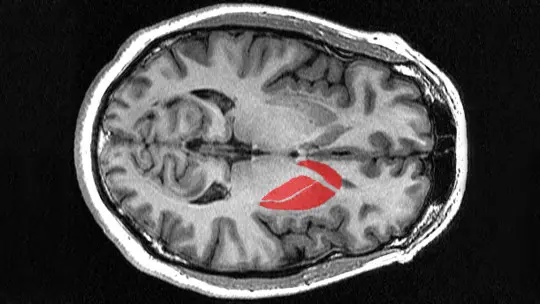

Let’s start with the basics, though even the basics here are more interesting than you might expect. The striatum is the largest structure within the basal ganglia—a collection of interconnected nuclei deep beneath the cerebral cortex. When neuroanatomists say “deep,” they mean it. The striatum sits well below the surface of the brain, nestled in subcortical regions where it can receive information from virtually everywhere in the cortex and send processed outputs to other deep structures that ultimately influence both movement and cognition.

The name “striatum” comes from its striped appearance when you slice it and look at it under basic staining. You see alternating bands of gray matter (neuron cell bodies) and white matter (myelinated axon fibers passing through). This striped pattern isn’t just decorative—it reflects the structural organization that allows the striatum to integrate inputs from across the brain. Those white matter fibers are the internal capsule, carrying information between cortex and subcortical structures, and they physically divide the striatum into distinct regions that have different but related functions.

Anatomically, the striatum divides into two main regions: the dorsal striatum and the ventral striatum. The dorsal striatum, which is what most neuroscientists mean when they say “striatum” without qualification, consists of two structures—the caudate nucleus and the putamen. The caudate nucleus is C-shaped, curving around following the contour of the lateral ventricles. It has a large head at the front, a body that extends back, and a tail that curves down and forward. The putamen sits more laterally, separated from the caudate by that internal capsule I mentioned. Together, the caudate and putamen handle cognitive and motor functions, which we’ll explore shortly.

The ventral striatum occupies the lower portion and includes the nucleus accumbens and the olfactory tubercle. The nucleus accumbens itself divides into a core and shell with slightly different connections and functions. This ventral region is intimately connected with limbic system structures and plays crucial roles in reward processing, motivation, and emotion—functions that have enormous clinical relevance for addiction, depression, and other mood disorders.

The striatum is a subcortical structure located deep within the brain, beneath the cerebral cortex. It sits in the forebrain on both the left and right sides, forming the largest component of the basal ganglia. Specifically, the caudate nucleus curves along the lateral ventricles, while the putamen sits more laterally, separated from the caudate by white matter tracts of the internal capsule. The nucleus accumbens, part of the ventral striatum, is located at the junction where the caudate and putamen meet at the front of the brain. Because it’s so deep in the brain, the striatum can’t be seen from the surface and is only visible in brain scans or dissected tissue. Its position at the center of multiple brain networks allows it to integrate information from cortical areas throughout the brain.